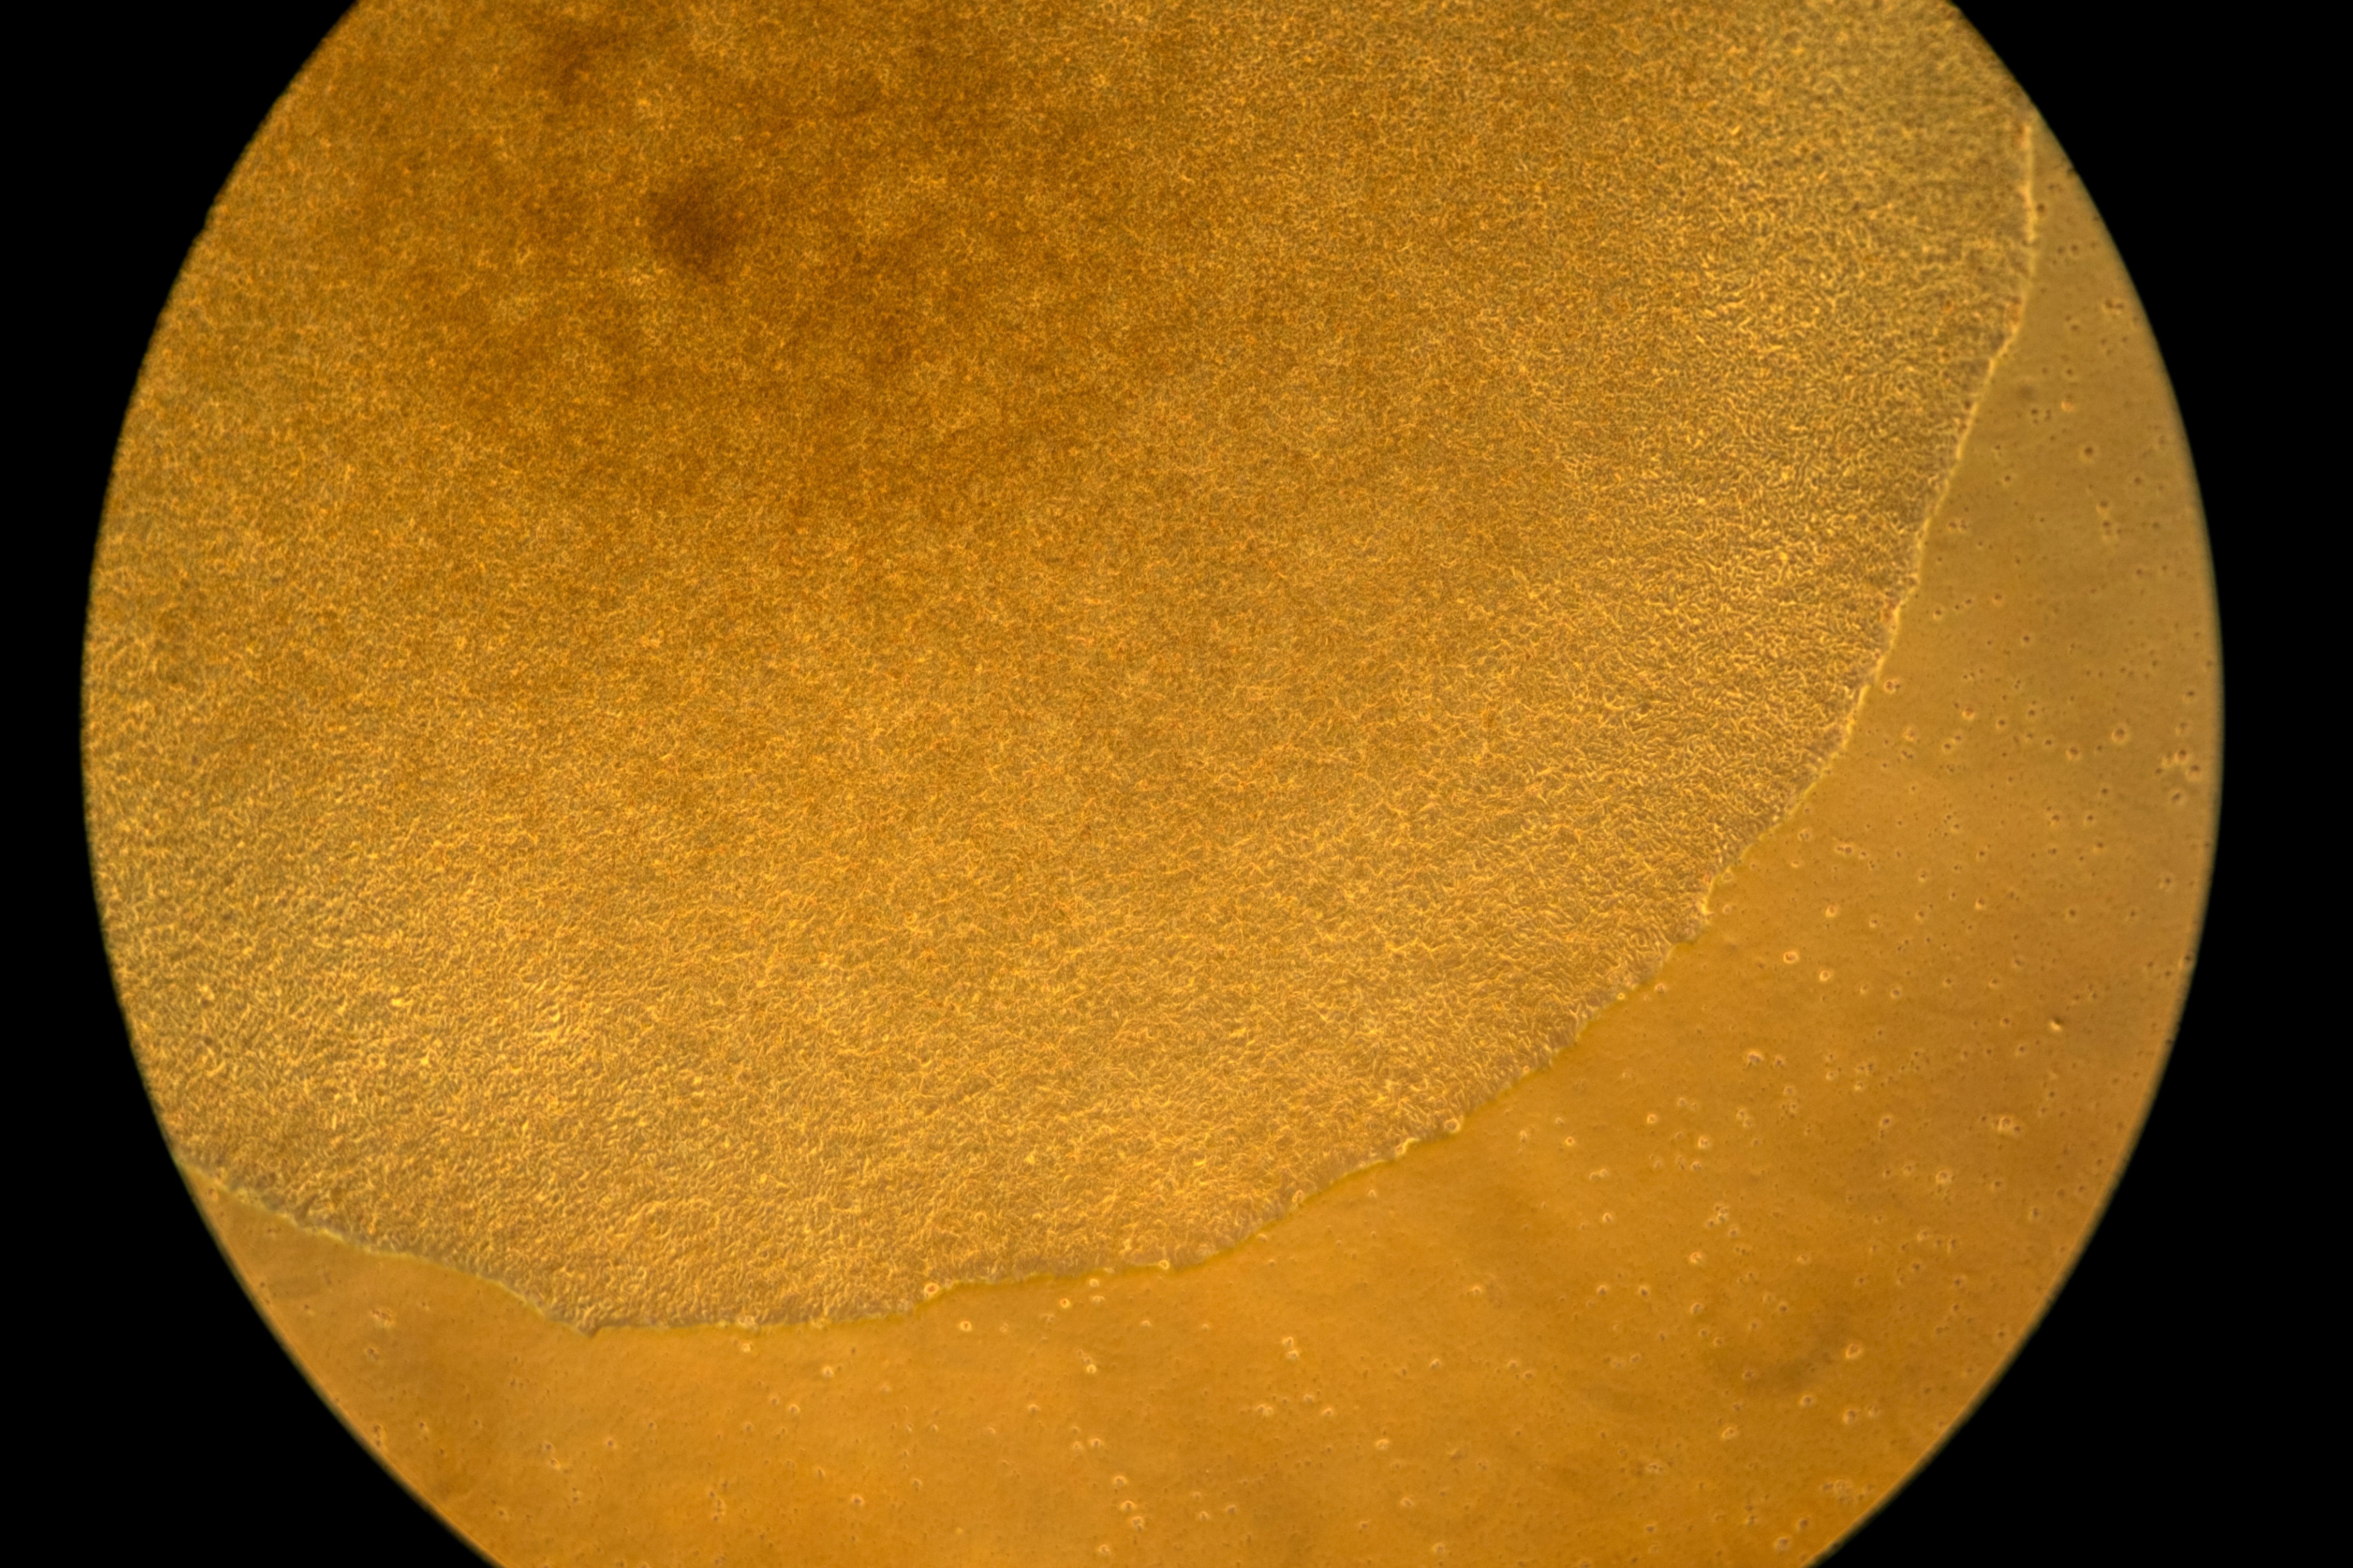

In Green's lab, a computer screen shines with brightly colored dots that resemble a galaxy. It’s a biological map that shows insulin-producing cells in the pancreas of a mouse. Red marks rogue T cells that destroy insulin production. Yellow indicates those peacemaker regulatory T cells — and they're outnumbered.

Green's team aims to use that mRNA to instruct certain immune “generals” to curb the bad T cells and send in more peacemakers. They package the mRNA in biodegradable nanoparticles that can be injected like a drug. When the right immune cells get the messages, the hope is they'd “divide, divide, divide and make a whole army of healthy cells that then help treat the disease," Green said.

The researchers will know it's working if that galaxy-like map shows less red and more yellow. Studies in people are still a few years away.